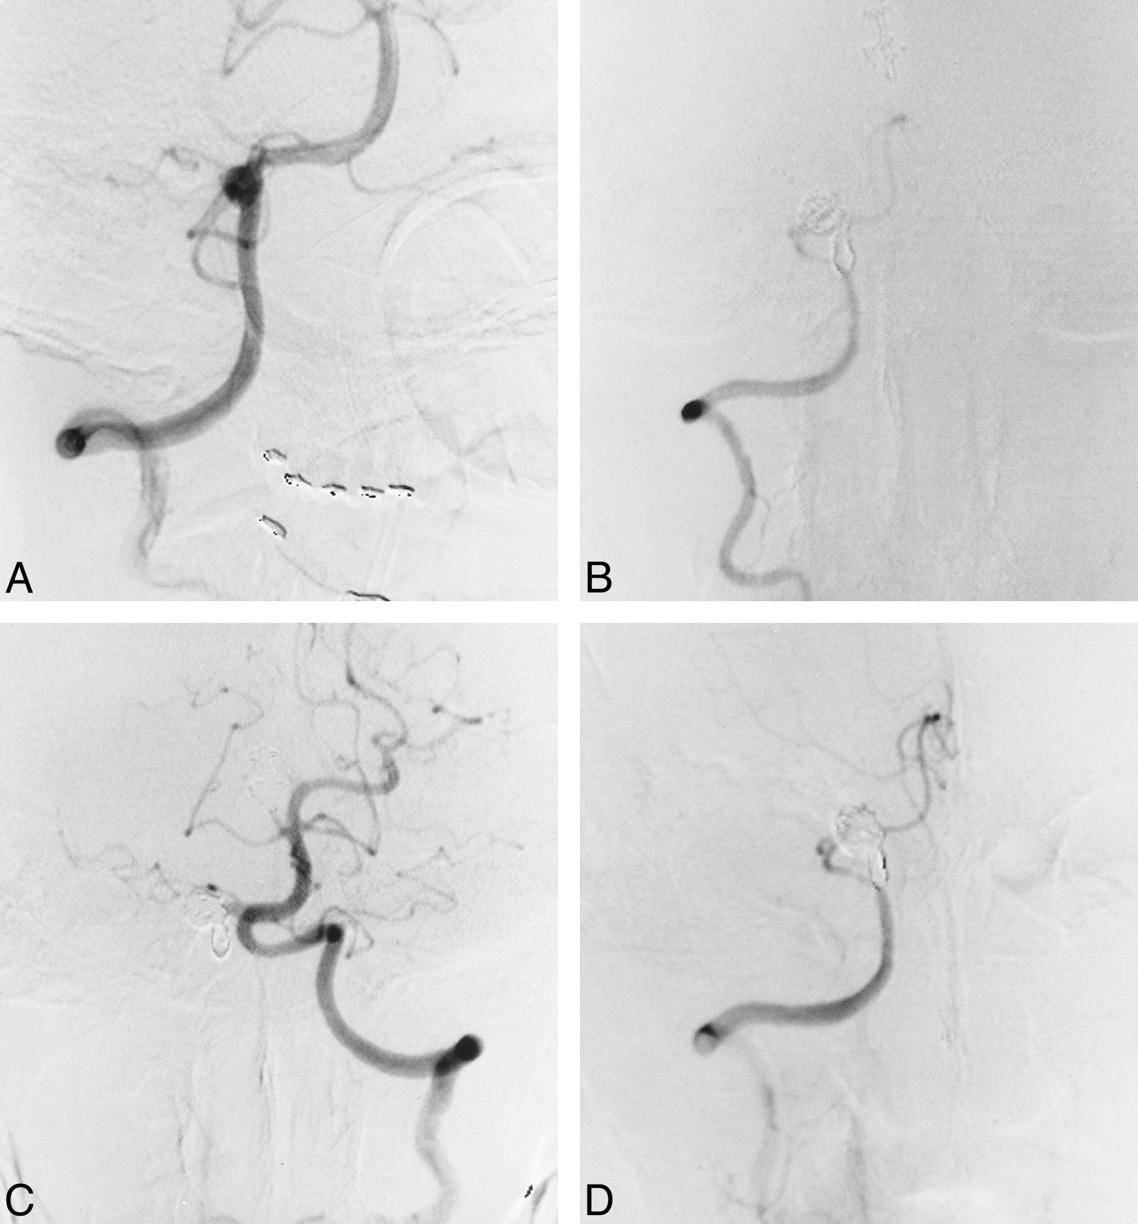

Case 5

A 58-year-old man presented with sudden onset of headache and vomiting followed by persistent severe neck pain at the hospital. The severe neck pain persisted, and a neurologic examination showed a Hunt and Kosnik grade of II. CT scans revealed subarachnoid hemorrhage in the cerebellopontine angle cistern, and right vertebral angiography on day 0 showed a vertebral artery dissecting aneurysm distal to the PICA origin (Fig 2A). The left vertebral artery could not be imaged by subclavian artery angiography, and conservative treatment was recommended. A second angiogram, obtained on day 8, showed recanalization of the left vertebral artery, with a mild stenotic origin. The possibility of bilateral dissection remained, but a third angiogram on day 15 showed persistence of blood flow and normal morphology of the left vertebral artery. Coil embolization for the right vertebral artery dissecting aneurysm was therefore advocated. A preceding balloon test occlusion of the right vertebral artery showed good retrograde blood flow, with a mean arterial stump pressure of 100 mm Hg (postocclusion mean arterial pressure [100 mm Hg] / preocclusion mean arterial pressure ratio: 91%). Repeat angiography after coil detachment showed no neurologic involvement at the dissection site (Fig 2B). The patient's clinical course after embolization was uneventful and he was discharged home with no neurologic deficit. Follow-up angiography 1 month after treatment showed complete occlusion of the dissection site (Fig 2C) and patency of the contralateral left vertebral artery (Fig 2D), confirmed by follow-up MR angiography 15 months after treatment.

Case 5.

A, Right vertebral artery angiogram, anterolateral view, shows a dissecting aneurysm distal to the PICA origin.

B, Right vertebral angiogram, anterolateral view, immediately after coil embolization of the dissection site.

C, Left vertebral angiogram, anterolateral view, shows an increase in diameter relative to that before embolization.

D, Follow-up right vertebral angiogram, anterolateral view, 1 month after embolization shows complete occlusion of the affected site and preservation of the PICA.